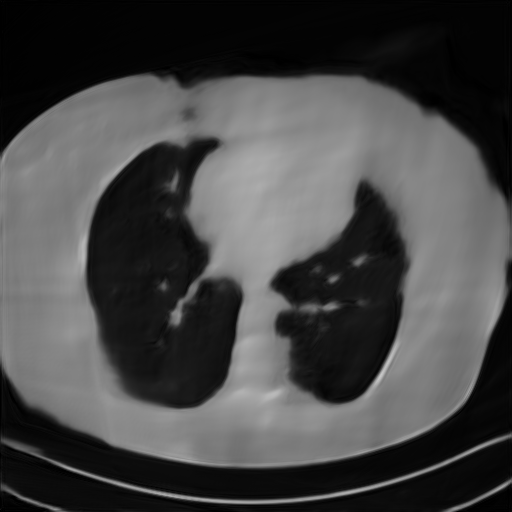

Fig. 4 presents the reconstruction results and residual images obtained by different methods for limited-angle reconstruction. As can be seen, the learning-based methods outperform the direct method and TV model, which exhibit serious artifacts in the missing angle region. Although the denoiser introduced by the FBP-Unet can somehow deal with the noises, the result still presents obvious artifacts. Compared to the SIPID, PD-net and FSR-nets, our LRIP-net1/2 can better preserve the image details and edges with less information left in the residual images. Thus, both the quantitative and qualitative results confirm that the low-to-high double-resolution strategy can improve the reconstruction accuracy for the limited-angle reconstruction problem.

We observe that the low-resolution image prior plays an important role in our method. More specifically, we compare the results of our LRIP-net with respect to different low-resolution priors, which are obtained by down-sampling rate of 1/2, 1/4, and 1/8, respectively. As can be seen in Table III, the best reconstruction results are obtained with the image prior reconstructed by the down-sampling rate of for 150∘, 120∘ and 90∘ limited-angle reconstruction. The visual comparison based on different image priors are also provided in Fig. 5, where obviously less artifacts are left in the reconstruction image by LRIP-net1/8. By comparing the running time, it is easy to see that the smaller the low-resolution image prior, the faster the LRIP-net works.